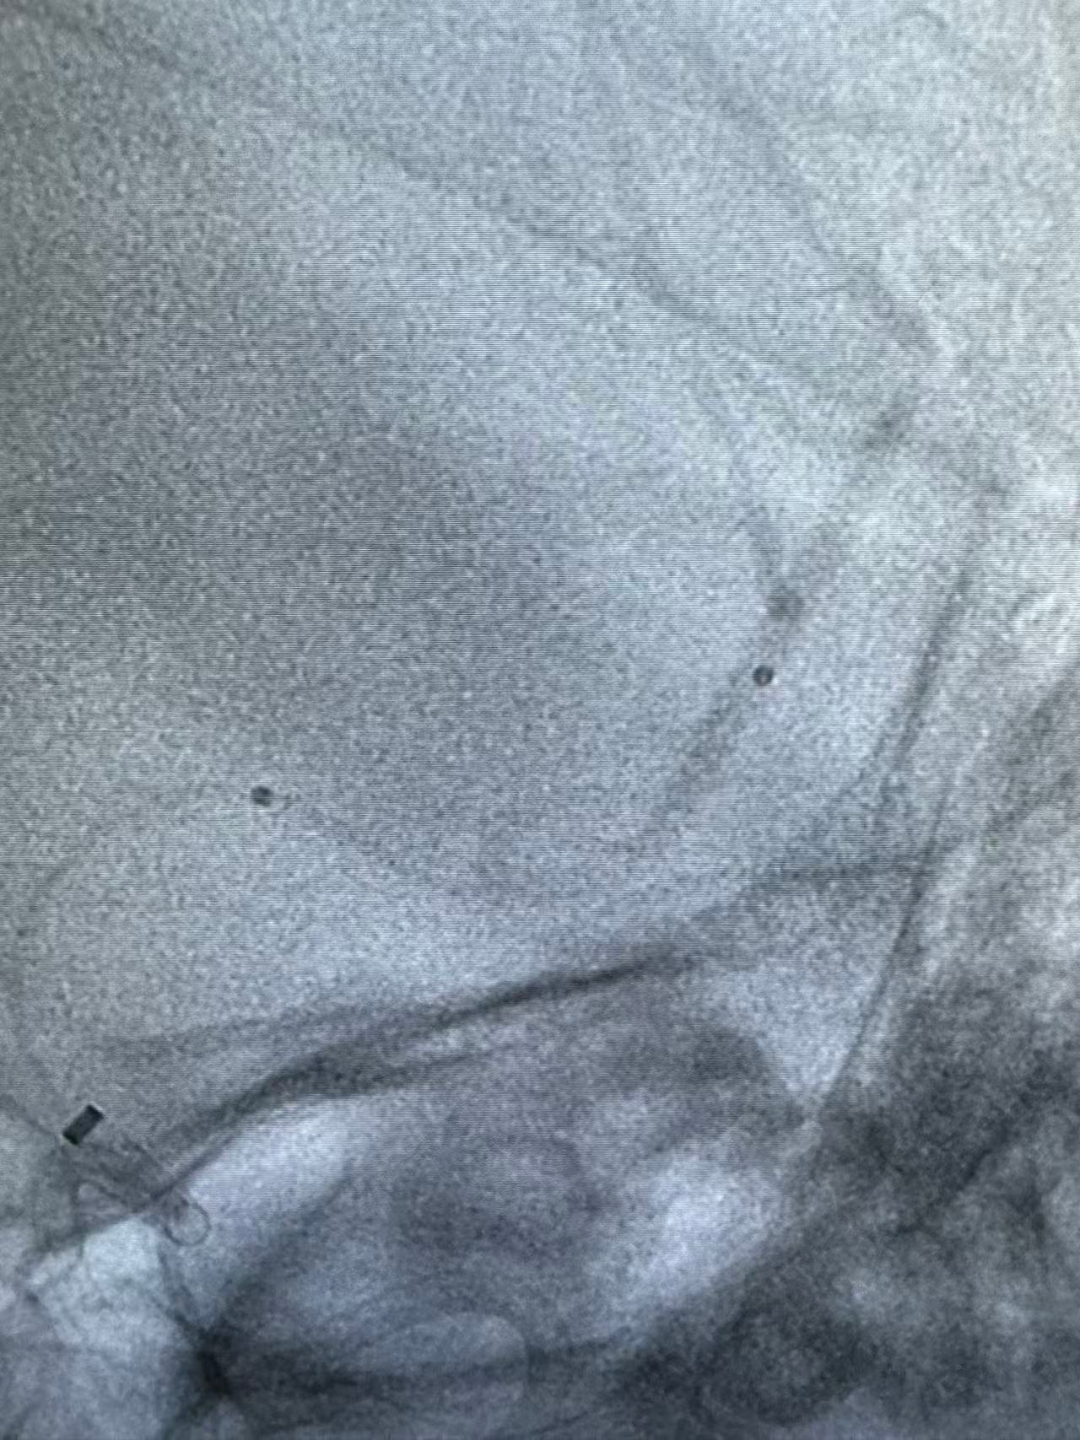

BMAX088球囊长鞘在泥鳅导丝及多功能管导引下顺利到达颈内动脉C1段。

微导丝微导管辅助下,6F中间导管前行,因海绵窦段血管较为迂曲,采用支架锚定跟进中间导管至血栓近端。

动脉长鞘怎么置入健谈•一鞘双能|温昌明教授团队:BMAX088球囊长鞘治疗左侧大脑中动脉闭塞一例_https://www.jmylbn.com_新闻资讯_第7张

动脉长鞘怎么置入健谈•一鞘双能|温昌明教授团队:BMAX088球囊长鞘治疗左侧大脑中动脉闭塞一例_https://www.jmylbn.com_新闻资讯_第8张